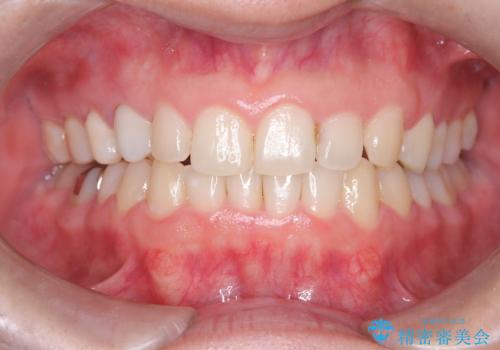

八重歯と正中のズレを解消!目立ちにくいワイヤー矯正で美しい歯並びへ

担当医 河口智英